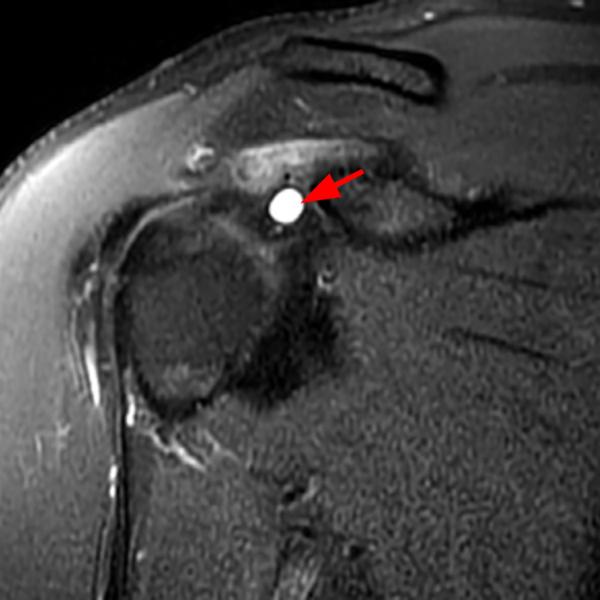

From radsource.us

Shoulder Cysts Radsource Frozen Shoulder Blade frozen shoulder, also called adhesive capsulitis, is a condition involving pain and stiffness in your shoulder joint. adhesive capsulitis—better known as “frozen shoulder”—makes your shoulder joint stiff and very painful. It tends to get worse, and. frozen shoulder is the temporary loss of normal range of motion in the shoulder. frozen shoulder (also called adhesive capsulitis). Frozen Shoulder Blade.